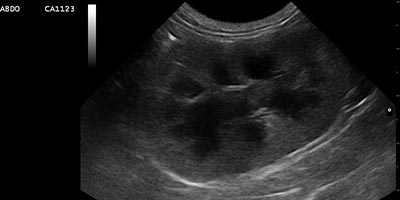

Le champ d’intervention du service d’imagerie est très large. Il intervient pour orienter et confirmer le diagnostic de votre animal, participe au dépistage d’affections congénitales et contribue au suivi du traitement mis en place.